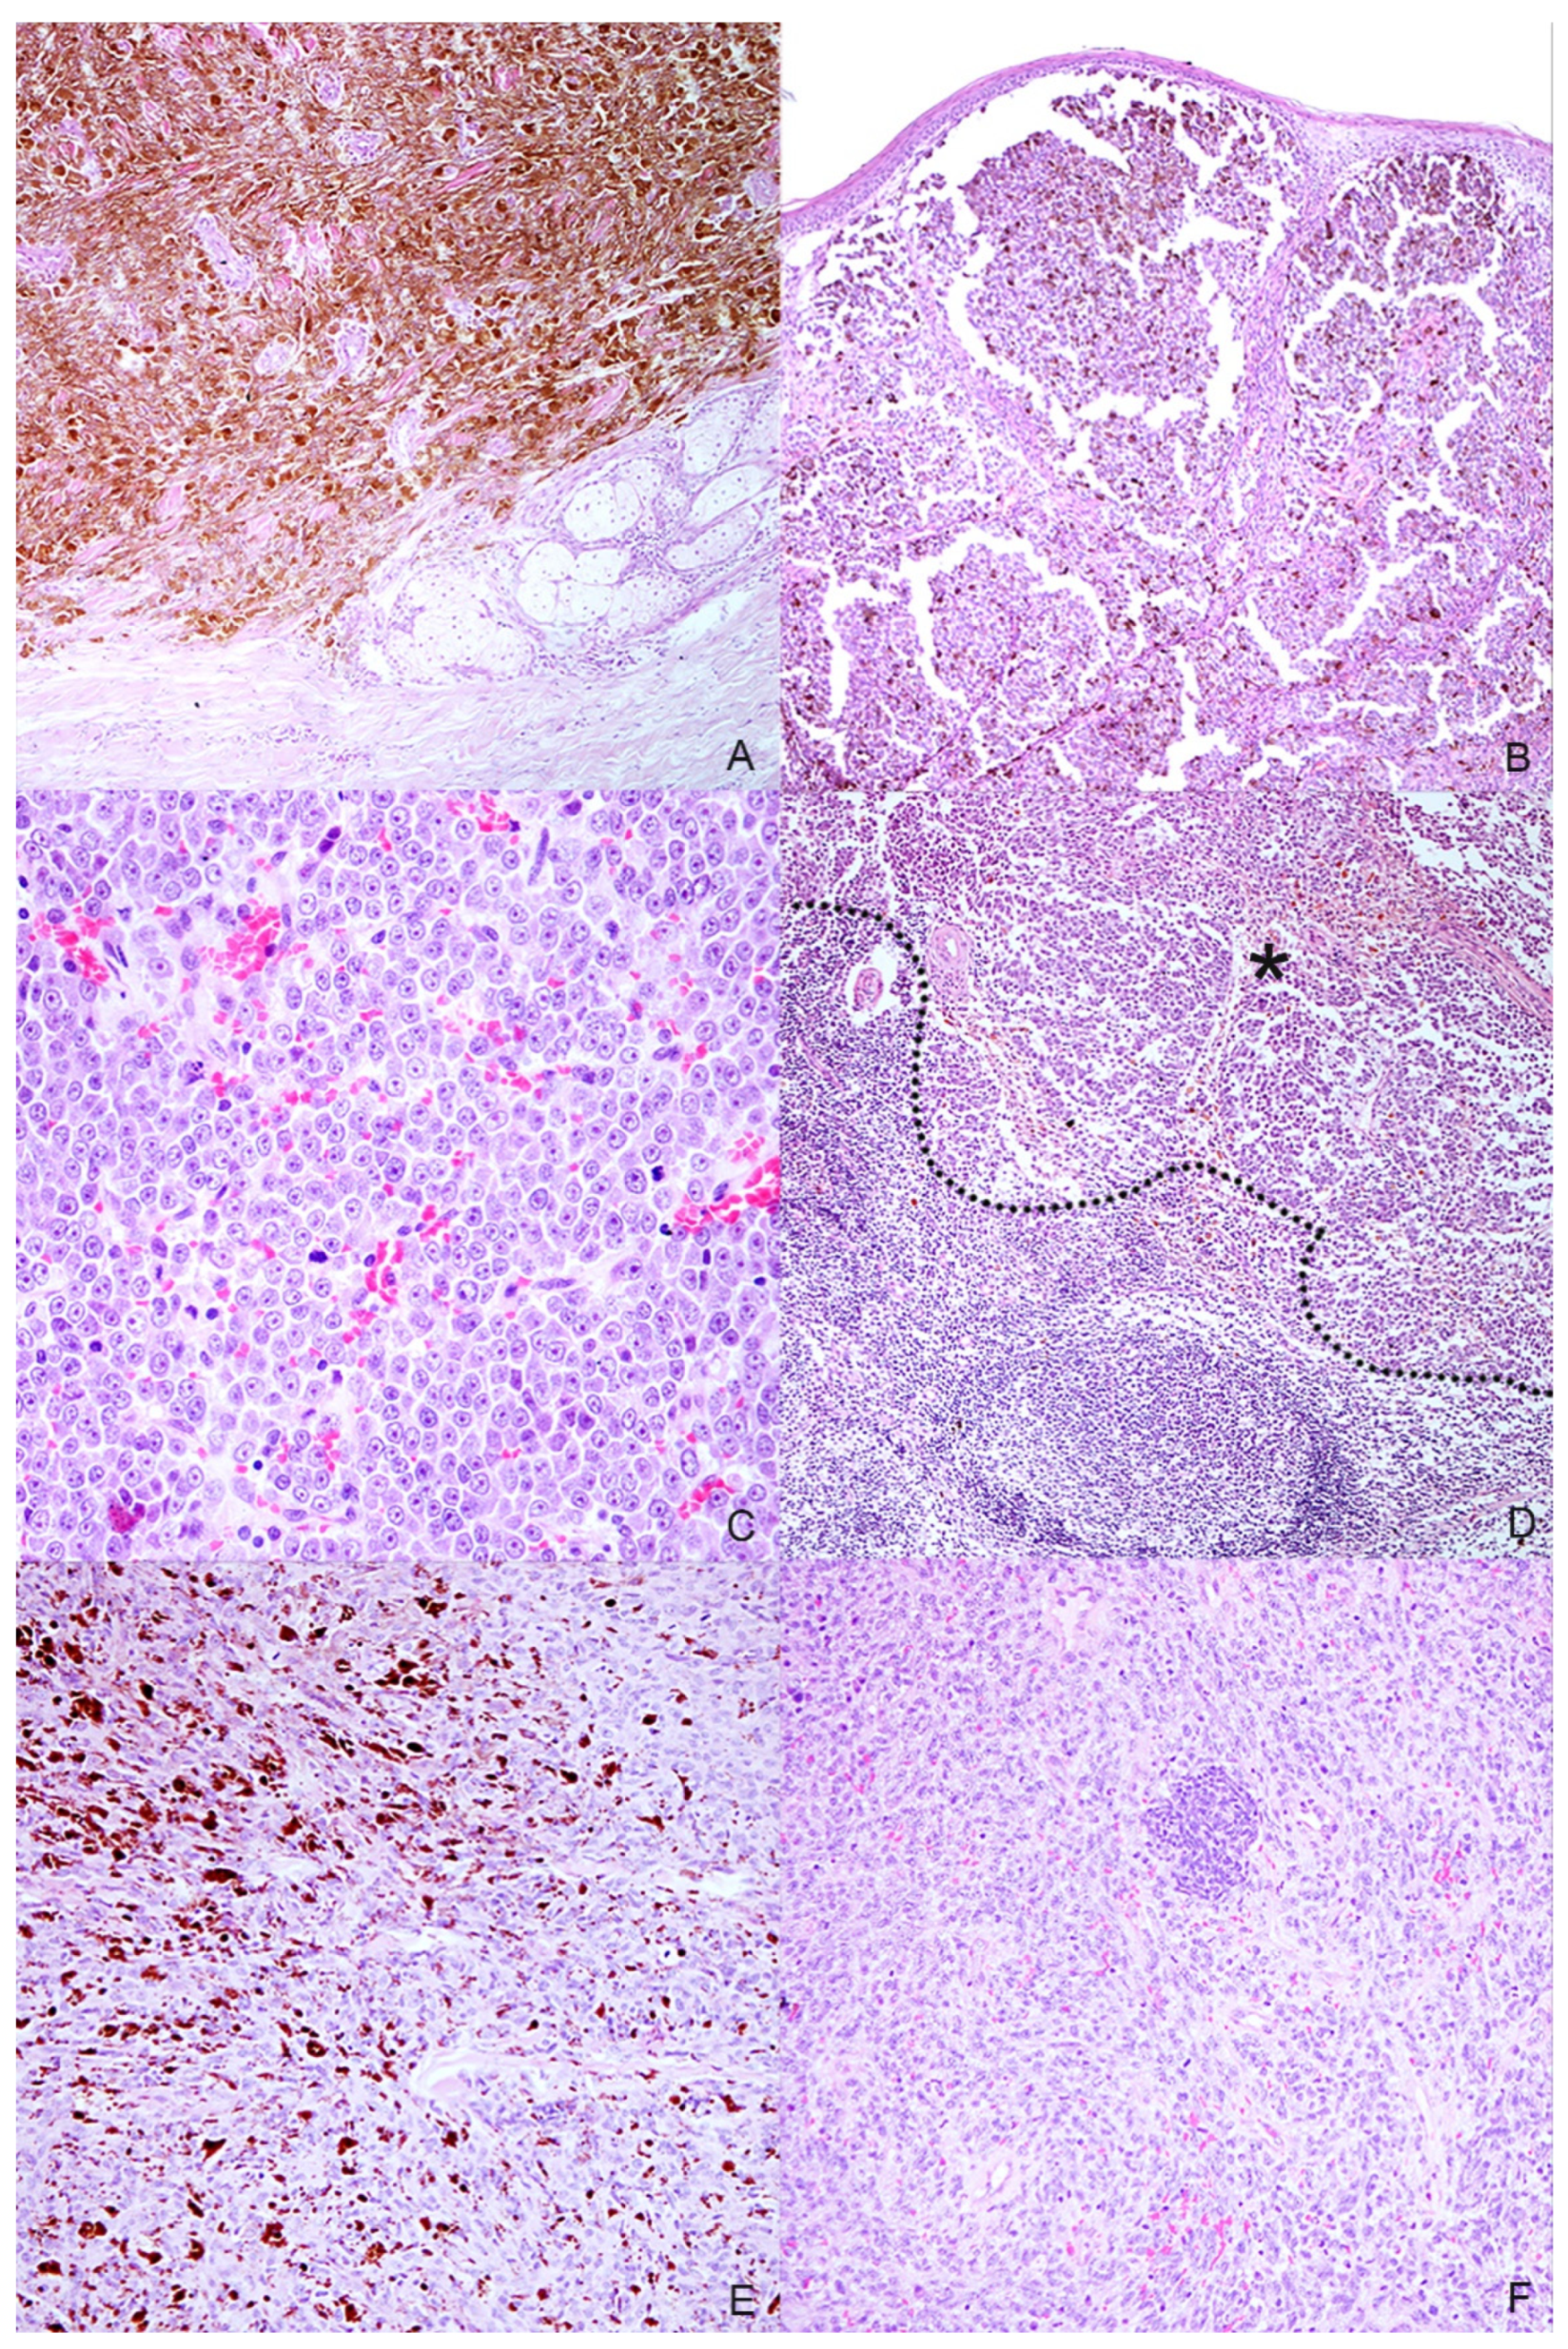

Figure 2.

Histopathologic characteristics of the selected melanocytic tumors. (A) Case n. 1—Dermal highly cellular proliferation of pigmented melanocytes with minimal cellular atypia (H-E, 100×); (B) Case n. 2—Densely packed, moderately pigmented melanocyte proliferation infiltrating the lamina propria of the oral mucosa(H-E, 100×); (C) Case n. 3—Mucosal amelanotic melanoma: cells show large nuclei with prominent nucleoli without intracytoplasmic melanin. Note the high mitoses (H-E, 400×); (D) Case n. 3—Lymph node metastasis: the same atypical melanocytic population effacing the architecture of the lymph node (residual cortical tissue on the bottom-left of the dotted line; metastatic tumoral tissue on the asterisk) (H-E, 100×); (E) Case n. 4—Spindle-shaped, frequently pigmented melanocytes proliferation with moderate cellular atypia, localized in the dermis (H-E, 200×); (F) Case n. 5—Mucosal amelanotic melanoma: epithelioid to polygonal neoplastic melanocytes forming sheets and rare nests in the lamina propria (H-E, 200×).

Eight samples were initially collected; however, three cases were excluded during processing because the subsequent histological and immunohistochemical investigations did not confirm the melanocytic origin of the tumor, diagnosed cytologically. Anamnestic data and histological classification of the selected five cases are reported in Table 1. Of the 5 cases, 2 were mixed breed and other 3 dogs were purebred dogs (English setter, German shepherd and Dobermann); 2 dogs were male and 3 female. Cutaneous tumors were localized in the interdigital space and flank, while mucosal ones originated from different sites of the oral cavity and the labial mucosa (Figure 1). Histology supported the melanocytic origin of the tumors and 1 cutaneous melanocytoma, 1 cutaneous melanoma and 3 mucosal melanoma were identified (Figure 2). Immunohistochemical investigation with antibodies against Melan A and PNL2 confirmed the morphological diagnosis in formalin-fixed, paraffin-embedded tissues. At the time of surgical excision of the tumor, only one dog with a mucosal melanoma (Case n. 3) had metastases to the mandibular and retropharyngeal lymph nodes.